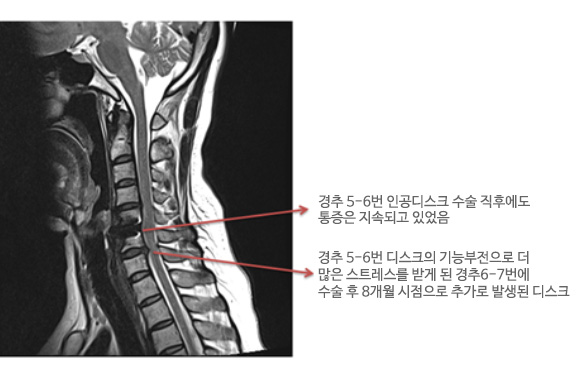

목디스크 증상이 지속적으로 약물이나 물리 치료로 개선되지 않는 경우, 수술을 고려해야 합니다. 수술은 통증이 심하거나 일상 생활에 큰 지장을 초래하거나 신경증상이 악화되며 근력이 감소할 때 필요한 선택이 될 수 있습니다. 또한, 큰 디스크가 탈출하여 중추 신경 척수를 압박하면 척수증이 나타날 때에도 수술을 고려해야 합니다.

주로 사용되는 수술 방법은 목의 앞쪽에서 디스크를 완전히 제거하고, 뼈 이식을 하는 것입니다. 만약 디스크가 세 군데 이상에 걸쳐 있는 경우에는 목의 뒤쪽에서 수술하는 방법이 효과적일 수 있습니다. 수술 후에는 일반적으로 6주에서 3개월 동안 목 보조기를 착용하는 것이 권장됩니다.